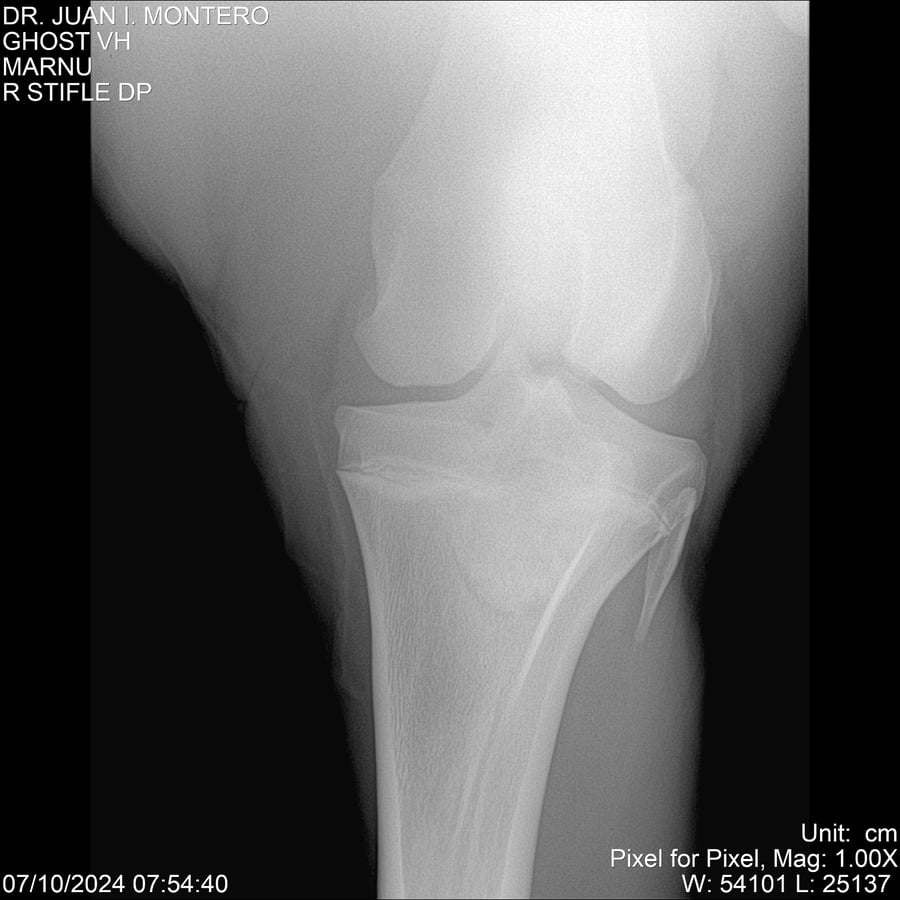

LOTE 15, GHOST VH 🔥 🔥 🔥 Lote Anterior Volver al remate Lote Siguiente Ficha Contacto Montevideo - Ficha del Lote Identificador: #282525 Categoría: Yeguarizos Montevideo - 69 Visualizaciones ClicData Contacto Empresa: Abelenda N. R., Walter Hugo Nombre*: Teléfono* : E-mail* : Mensaje Enviar Registrese gratis Este contenido Exclusivo está disponible sólo para usuarios registrados Ingresar